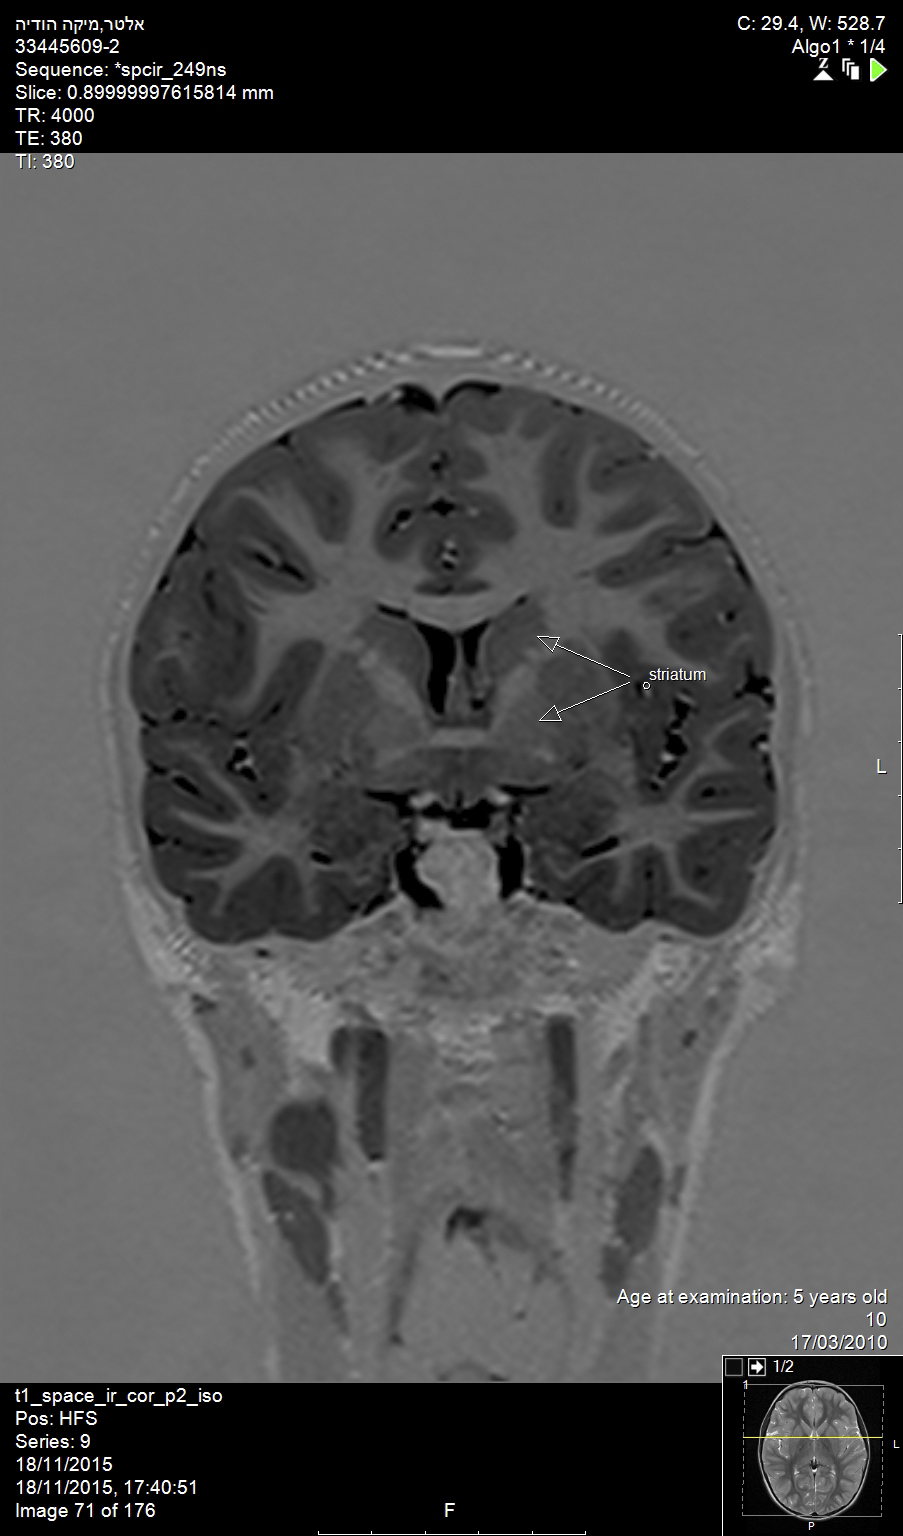

Huntington’s disease is named after George Huntington, the physician who described it as hereditary chorea in 1872. It is an incurable, adult-onset, autosomal dominant inherited disorder associated with cell loss within a specific subset of neurons in the basal ganglia and cortex.3 The most striking neuropathology in Huntington’s disease occurs within the neostriatum (Figure 2), in which gross atrophy of the caudate nucleus and putamen (Figure 3) is accompanied by selective neuronal loss and astrogliosis. Marked neuronal loss is also seen in deep layers of the cerebral cortex.4 The clinical features include a movement disorder, cognitive disorder, dementia, and behavior disorder. Patients may present with one or all disorders in varying degrees.5

Fig 2. This MRI shows the neostriatum in the brain of a child (arrows: striatum).

Figure 2